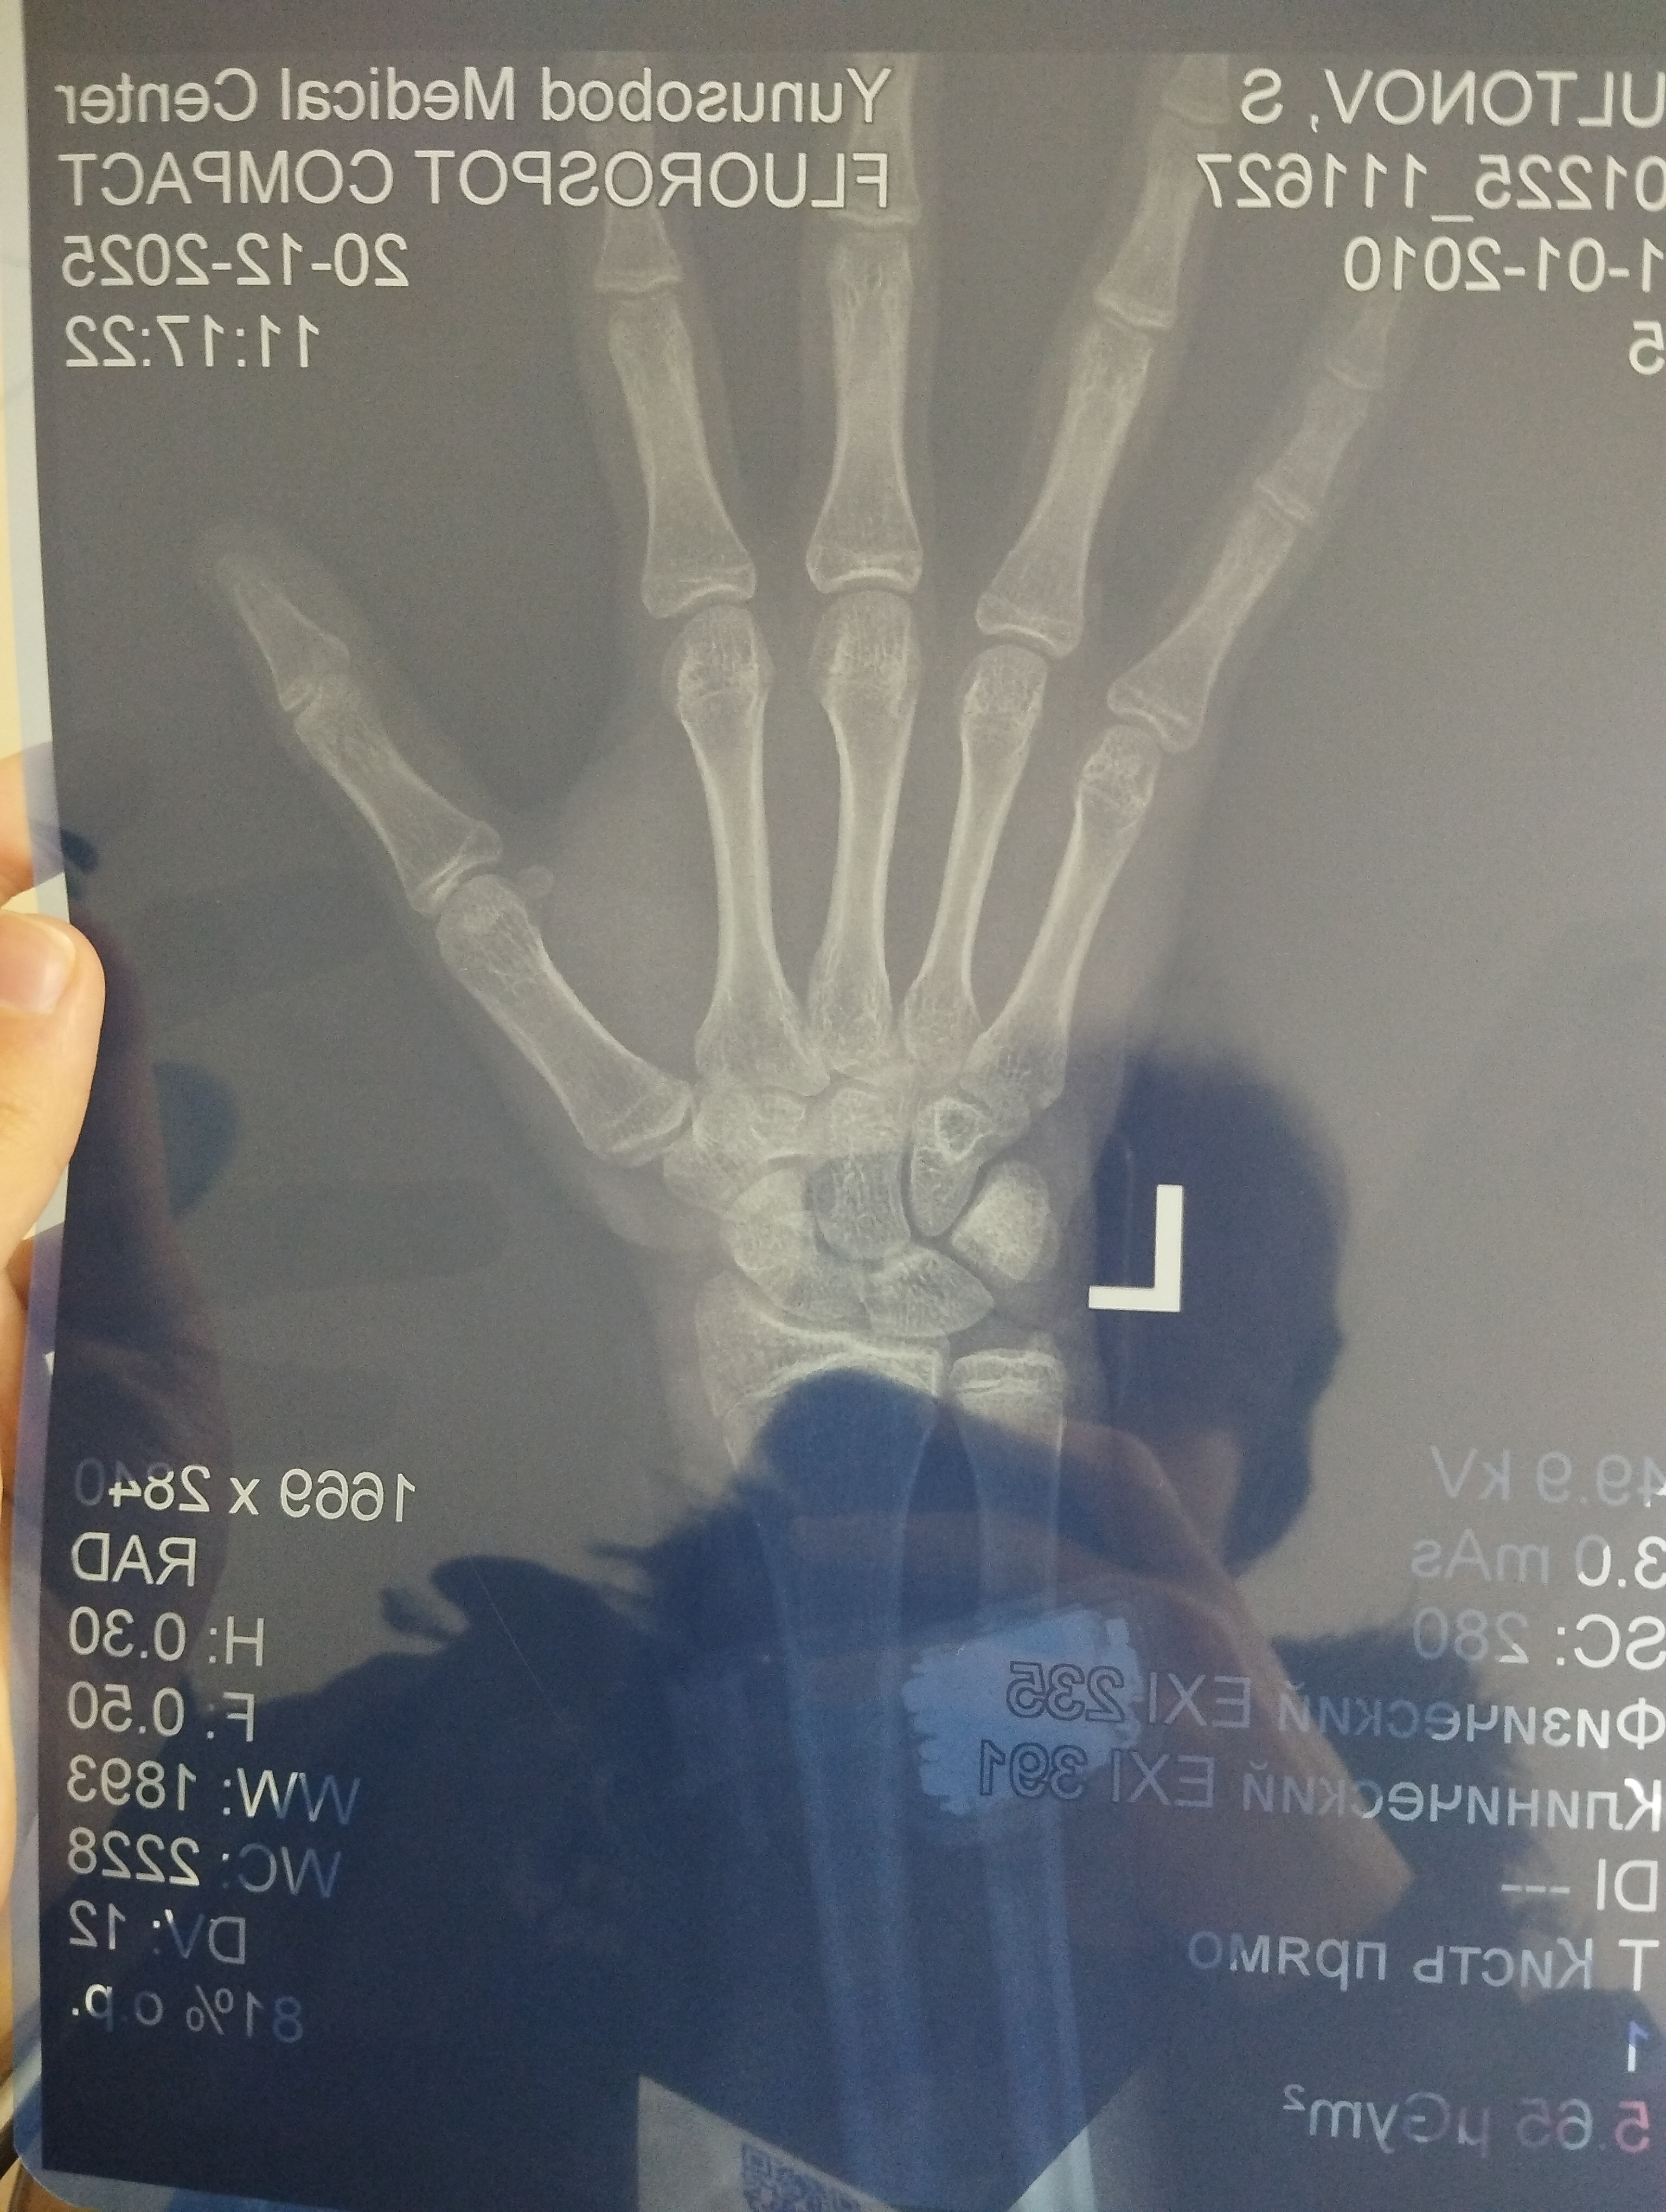

i did rengen and it said my growth plates are slightly opened, and my skeleton age is 16 yo. i am 173 cm, same as my dad an mom is 160, whats my final height?

It looks like the growth plates are barely open.

Phalanges & Metacarpals growth plates appear to be mostly closed. your growth plate for the radius is beginning to fuse, the ulna is Also showing advanced mineralization. I would guess your making it to about 175-176 by the time your 18.